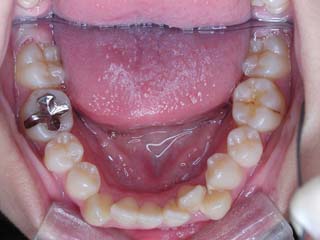

主訴:上の歯が出ている

診断名:顎関節症、下顎左右5欠損を伴う骨格性上顎前突

年齢:35歳

使用した主な装置名:TPB、マルチブラケット装置

抜歯/非抜歯および抜歯部位:非抜歯

治療期間:動的処置2年、経過観察3年

費用の目安:保険適応 自己負担金として30~50万

リスク、副作用:外科手術によるリスク、マルチブラケット治療に伴う歯根吸収など偶発症が発生するリスクがある。

強い骨格性の上顎前突が見られます。しばしば、口腔内所見では骨格のズレを歯の補償的な傾斜などでカムフラージュさせているため、あまり大したことのないズレにしか見えない事があります。また、上顎前突の場合は、下顎が関節の位置で知らず知らずのうちに前方へ大きく偏位させて噛んでいる事が多いです。このような場合は、咬合器に装着してみて初めて、治療方針が見えてくるかもしれません。どのような不正咬合であれ、大きなズレに対しては、外科的に骨のズレを改善する治療が理にかなっています。前後のズレ、垂直のズレと条件が重なってきた場合、より外科矯正での改善が望ましいでしょう。

一般的な外科矯正治療の流れは、術前矯正・外科矯正・術後矯正・保定治療と移行します。術後矯正では、手術後に僅かに見られる後戻りに対する処置や、刻々と変化する額関節の環境に対応して調節を続けます。特に大きな問題が無ければ6か月程度で保定治療に移行します。